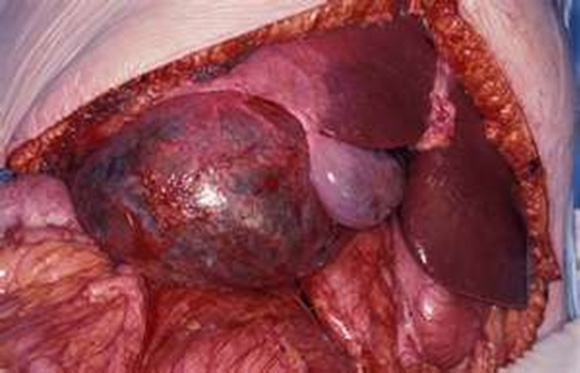

Οι απλές ηπατικές κύστεις ανιχνεύονται στο 4% του πληθυσμού και είναι τέσσερεις φορές συχνότερες στις γυναίκες (εικόνα 1). Τις περισσότερες φορές είναι εντελώς ασυμπτωματικές. Όταν αποκτήσουν μεγάλο μέγεθος (> 10 cm), μπορεί να προκαλούν πιεστικά φαινόμενα στο διάφραγμα (δυσκολία στην αναπνοή) ή στο στομάχι (έμετοι). Επιπλέον, ελάχιστες φορές μπορεί να επιπλακούν με ενδοκυστική αιμορραγία (συνήθως συνοδεύεται από οξύ πόνο), να αποφράξουν τα παρακείμενα χοληφόρα αγγεία (ίκτερος) ή να επιμολυνθούν (πυρετός). Δεν εξαλλάσσονται ποτέ σε καρκίνο. Εξαιρετικά σπάνια και μόνο στην περίπτωση της πολυκυστικής νόσου νεφρών-ήπατος οδηγούν σε ηπατική ανεπάρκεια.

Εικόνα 1. Απλή μονήρης κύστη του δεξιού ηπατικού λοβού σε γυναίκα 58 ετών. Η ασθενής υποβλήθηκε σε απεικονιστικές εξετάσεις κοιλίας ύστερα από επεισόδιο έντονου πόνου στο δεξιό υποχόνδριο και σημαντικής πτώσης του αιματοκρίτη. Εγχειρητικά επιβεβαιώθηκε η διάγνωση της αυτόματης ενδοκυστικής αιμορραγίας.